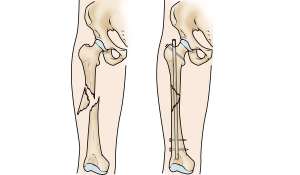

Стегнова кістка є найбільшою і найміцнішою кісткою у людському тілі. Її переломи можуть траплятися під час падінь, нещасних випадків, падінні важких об’єктів на ногу. Збільшує ризик перелому дегенеративна хвороба кістки, наприклад остеопороз, який спричиняє втрату міцності і щільності кісток.